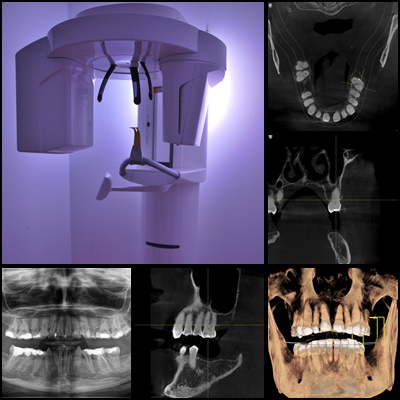

Ortopan (panoramska radiografija)

Ortopan, ili panoramska radiografija, je dentalna 2D rendgenska snimka donje trećine lica. Omogućava detaljan pregled svih zuba, čeljusti, sinusa i okolnih struktura. Ova snimka neizostavan je dio prvog stomatološkog pregleda, kao i redovnih godišnjih kontrola.

CBCT – dentalni 3D snimak

CBCT (Cone Beam Computed Tomography) je dentalna 3D snimka vrlo niskog zračenja, koja pruža trodimenzionalni prikaz čeljusti i zuba. Ova metoda omogućava izuzetno preciznu dijagnozu te je posebno važna za planiranje implantoloških i oralno-kirurških zahvata.

Ovisno o potrebama zahvata, dostupne su različite veličine polja snimanja:

- snimanje jednog zuba

- segmentno snimanje

- snimanje jedne čeljusti

- snimanje obje čeljusti